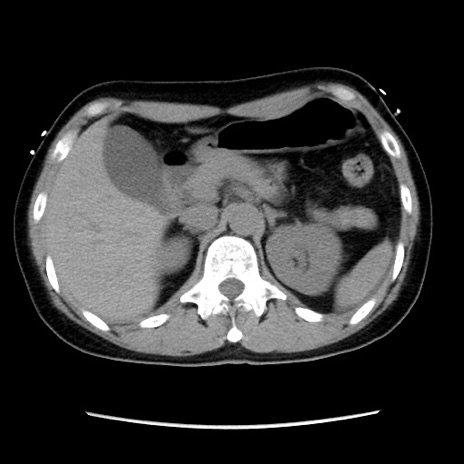

症例10(横断像)

【症例】 50歳代女性

【主訴】 腹痛

【現病歴】前日生レバーを食べた。今朝に排便あり。 昼前に突然発症の腹痛を生じ、当院救急外来を受診した。

【身体所見】 意識清明、腹部:平坦、軟、下腹部やや左を中心に圧痛・反跳痛あり、筋性防御あり

【データ】WBC 7800、CRP 0.07